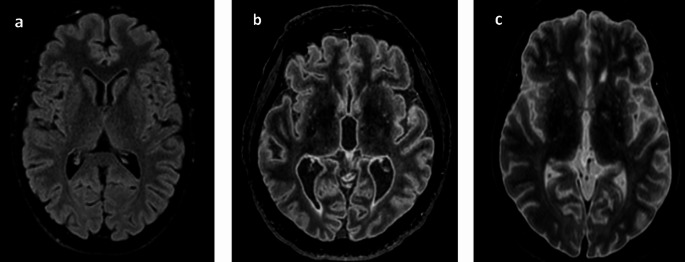

Introduction: Postmortem magnetic resonance imaging (PMMR) has gained importance during the last decade in forensic pathology. While many clinical radiology sequences are applicable for the evaluation of the brain, the 3D FLAIR sequence shows different contrast in postmortem cases compared to living patients. Two factors-the temperature and the interval between official declaration of the death and PMMR (DC-PMMR interval) are suspected to influence the optimal inversion time (TI) needed to achieve living patient-like image contrast. This study aimed to investigate if our empirical approach had the same results as previous study.

Materials and methods: 3D FLAIR sequences with varying TI values (from 1660 ms to 900 ms, every 110 ms) were acquired. Two radiologists independently assessed the images, selecting the TI that produced the most patient-like contrast. Rectal temperature and the DC-PMMR interval were recorded, and Pearson correlation tests were conducted to evaluate interrelations between TI, temperature, and DC-PMMR interval. Interobserver reliability was assessed using PABAK.